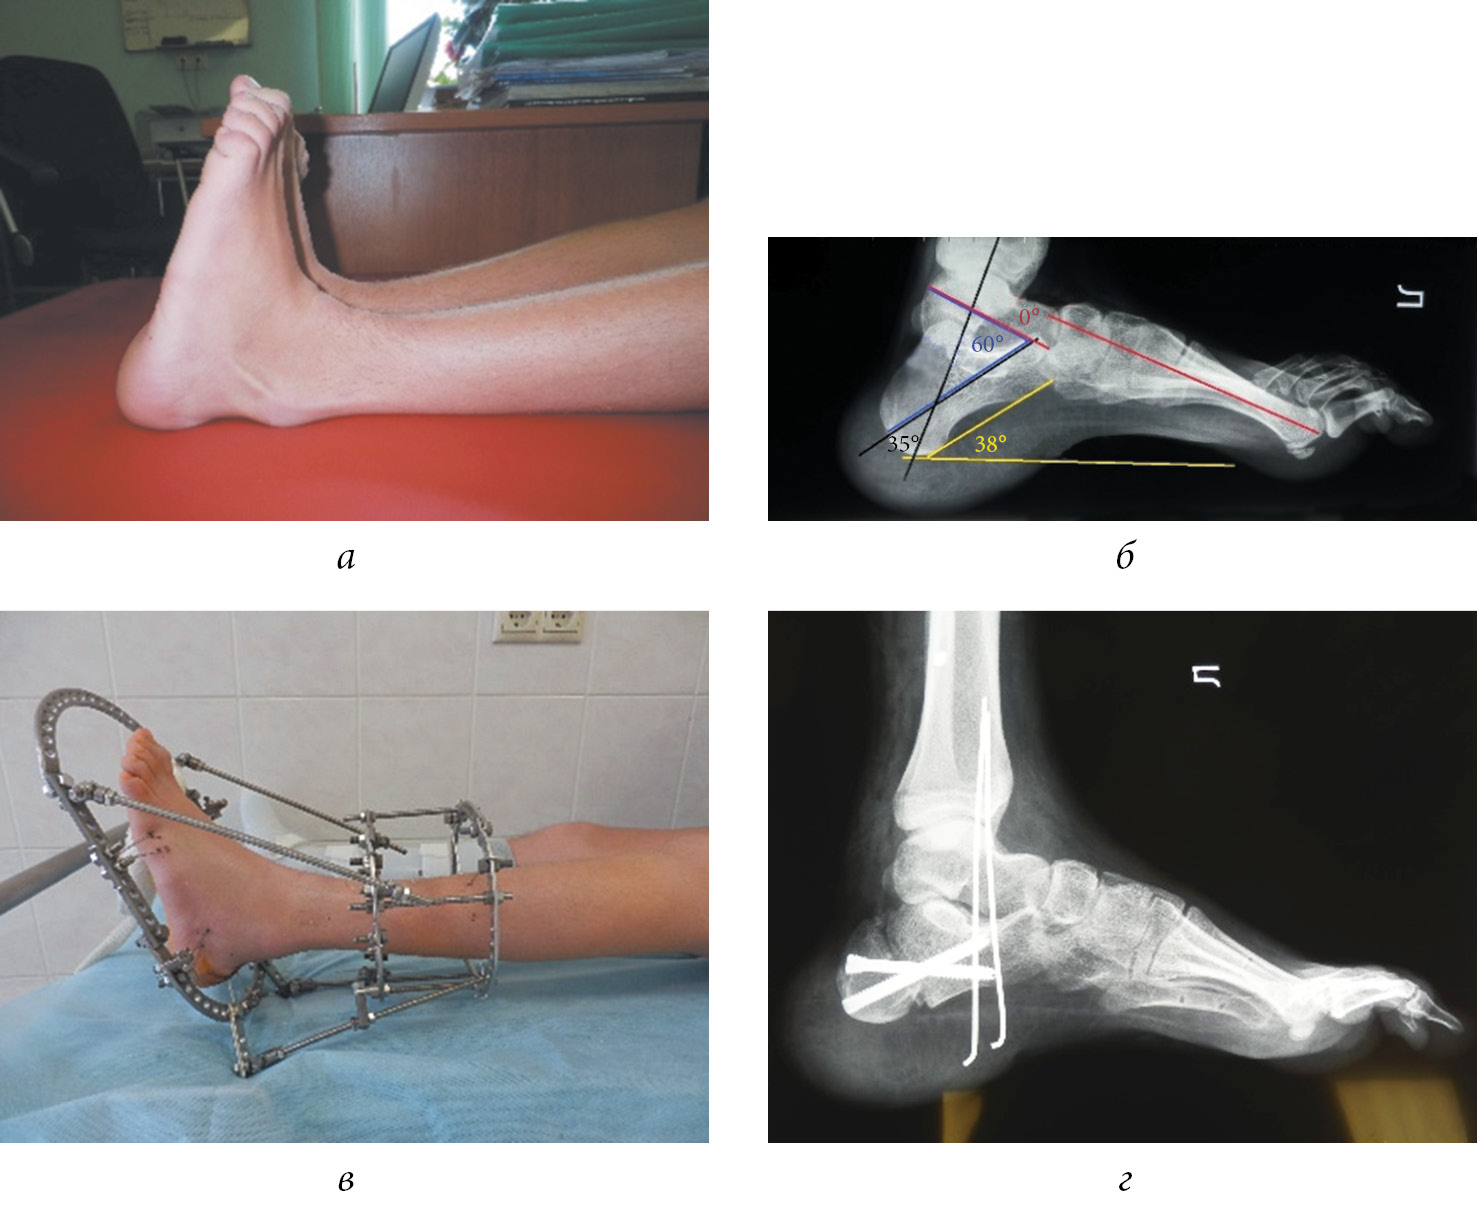

Clinical example (Fig. 3). Patient A., 15 years old. The patient was diagnosed with meningomyeloradiculocele of the lumbosacral spine. Neurogenic calcaneal deformity of the feet. Upon admission, the foot was extended at 25°, and flexion of the foot was impossible. During manual testing, the feet are brought to the middle position with difficulty, with a pronounced tension of the soft tissues of the dorsum of the foot, dyscirculatory disorders (tissue ischemia), and the toes are placed in a curved position due to the tension of shortened extensor tendons. Muscle strength is represented by the anterior tibial muscle on the right and left at 5 points, the fibular muscles are 3 points on the right and 1–2 points on the left, and the rear group of the lower leg muscles on the right and left are 0 point. The radiograph of the left foot upon admission shows 35° for the calcaneotibial angle, 38° for the calcaneal pitch, 60° for the sagittal astragalocalcanean angle, and 0° for Meary’s angle. Considering the tension of soft tissues, the first step in constriction of extensor tendons to reduce the risk of trophic disorders was applying the Ilizarov apparatus on the left foot and lower leg. The deformity was partially corrected in the process of distraction, and 20° flexion of the foot was achieved. At the second stage, corrective sliding osteotomy of the calcaneus was performed with fixation with Qwix screws, transposition of the tendons of the anterior tibial muscle and the short peroneal muscle, and Achilles tenodesis by Westin. On the postoperative radiograph of the left foot, calcaneal foot deformity was eliminated, with a calcaneotibial angle of 70°, calcaneal pitch of 20°, sagittal astragalocalcanean angle of 35°, and Meary’s angle of 0°. Load on the foot is allowed 3 months postoperatively. Subsequently, right foot deformity was corrected based on the same scheme.

Fig. 3. Patient A., 15 years old, with a diagnosis of meningomyeloradiculocele of the lumbosacral spine. Neurogenic calcaneal deformity of the feet: a — the appearance of the feet upon admission; b — radiograph of the left foot in lateral projection upon admission; c — the appearance of the foot in the first stage of treatment in the Ilizarov apparatus, flexion of the foot of 20° is achieved; d — radiograph of the foot in lateral projection after surgical treatment